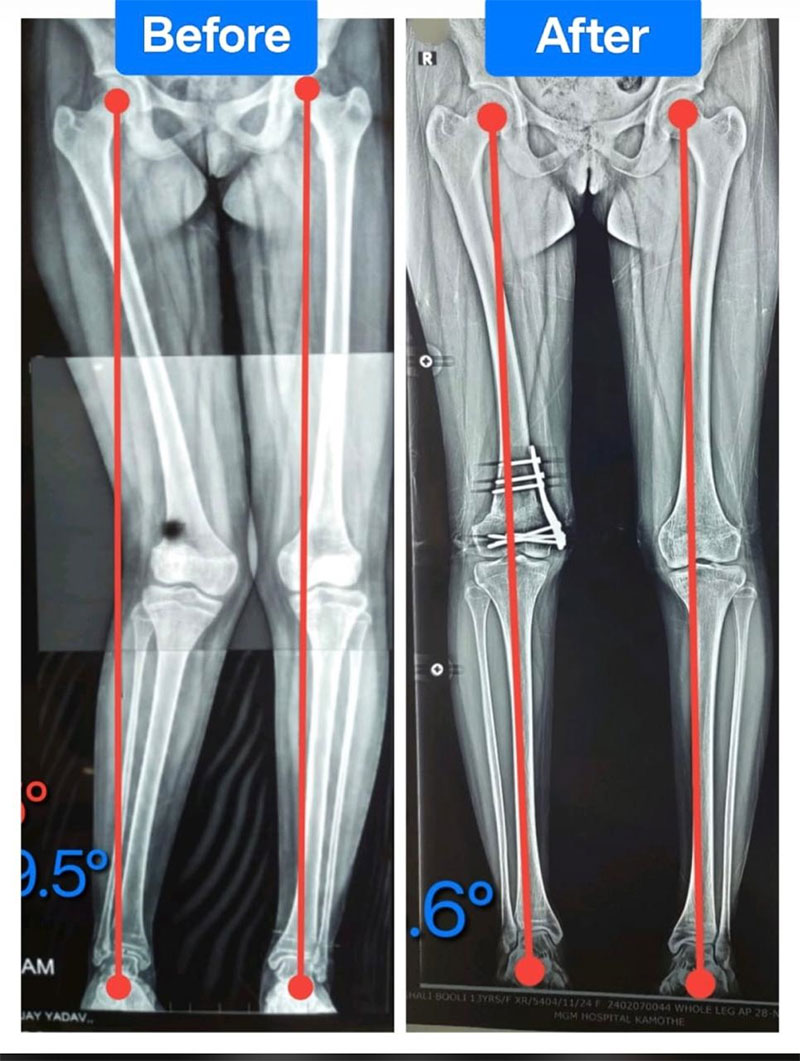

Deformity Correction